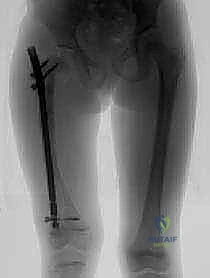

تُعد هذه العملية من أدق العمليات في جراحة عظام الأطفال، وتتطلب مهارة استثنائية كما هو الحال مع البروفيسور محمد هطيف. يتكون المسمار التلسكوبي (Fassier-Duval) من جزأين يتداخلان ببعضهما البعض (مثل التلسكوب). يتم تثبيت أحد الأطراف في أعلى العظم والطرف الآخر في أسفله. عندما ينمو العظم، ينزلق الجزء الداخلي من المسمار للخارج، مما يسمح للعظم بالنمو الطبيعي دون أن ينثني أو ينكسر.

الخطوة الثالثة: بضع العظم المتعدد عبر الجلد (Multiple Percutaneous Osteotomies)

بدلاً من فتح الساق بالكامل، يقوم الدكتور هطيف بعمل ثقوب صغيرة جداً (مليمترات) في الجلد. باستخدام أدوات دقيقة جداً (مثل الإزميل الدقيق أو المثقاب المتخصص)، يتم قطع العظم في أماكن التقوس من الداخل دون إتلاف الأنسجة الرخوة أو العضلات المحيطة. هذا يحافظ على التروية الدموية للعظم (Periosteum)، مما يسرع من التئام العظم بشكل مذهل.

الخطوة الرابعة: إدخال المسمار التلسكوبي

بعد تقويم العظم وجعله مستقيماً كحبات المسبحة على خيط، يتم إدخال السلك الدليلي (Guide Wire). ثم يتم إدخال الجزء الخارجي (الأنثوي) من المسمار التلسكوبي وتثبيته في الجزء العلوي من العظم (Epiphysis).

بعد ذلك، يتم إدخال الجزء الداخلي (الذكري) من المسمار عبر الجزء السفلي من العظم وتثبيته في المشاشة السفلية. هذا التصميم العبقري يضمن حماية العظم بالكامل من الداخل.

كان عمار يعاني من النوع الثالث من تخلّق العظم الناقص، مع تقوس شديد في عظمي الفخذين (بشكل حرف O) منعه من المشي تماماً، وجعله حبيس الكرسي المتحرك، مع تاريخ من 8 كسور سابقة. تم إجراء عملية بضع العظم المتعدد عبر الجلد وتركيب مسامير فاسييه-دوفال التلسكوبية في كلتا الساقين في جلسة جراحية واحدة بواسطة الدكتور هطيف. اليوم، وبعد 6 أشهر من الجراحة، يمشي عمار مستقلاً لأول مرة في حياته، ولم يتعرض لأي كسر جديد.